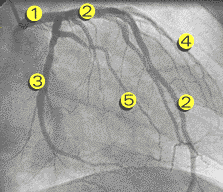

Cineangiocoronariografia: visualização da luz das artérias coronárias com a substância contrastante ao Rx, em filme de 35mm.

1 - Tronco da Coronária Esquerda

2 - Ramo Descendente Anterior

3 - Ramo Circunflexo

4 - Ramo Diagonal

5 - Ramo Marginal